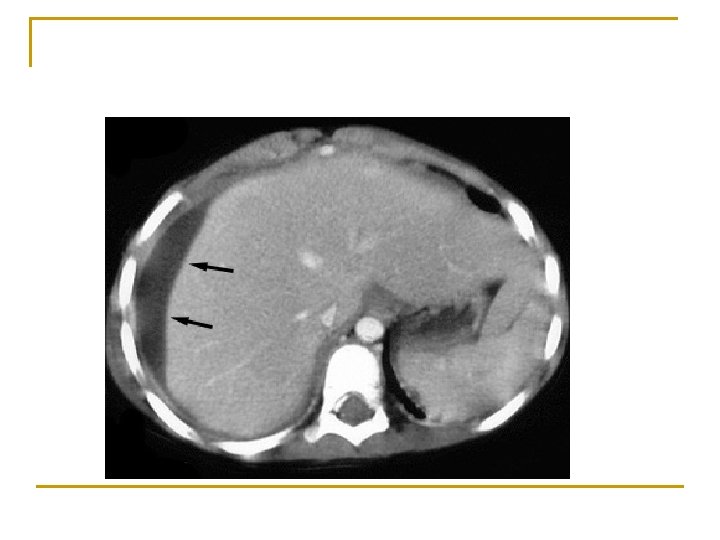

Karaciğer apseleri n n Genellikle piyojenik bakterilere bağlı gelişir. İnsidansı düşüktür (% 0. 013 -0. 035) Karaciğer apsesi soliter (%50) ya da multipl (biliyer kaynaklı) olabilir. Sağ, sol, kaudat lob

Tanı n n n Lökositoz (% 84 -88), ALP yüksekliği (% 60); diğer karaciğer fonksiyon testleri belirleyici değildir. Karın USG ve BT, kan kültürü (% 60 pozitif), apse kültürü. . . Multipl küçük apseler soliter apselerden daha mortal seyreder.